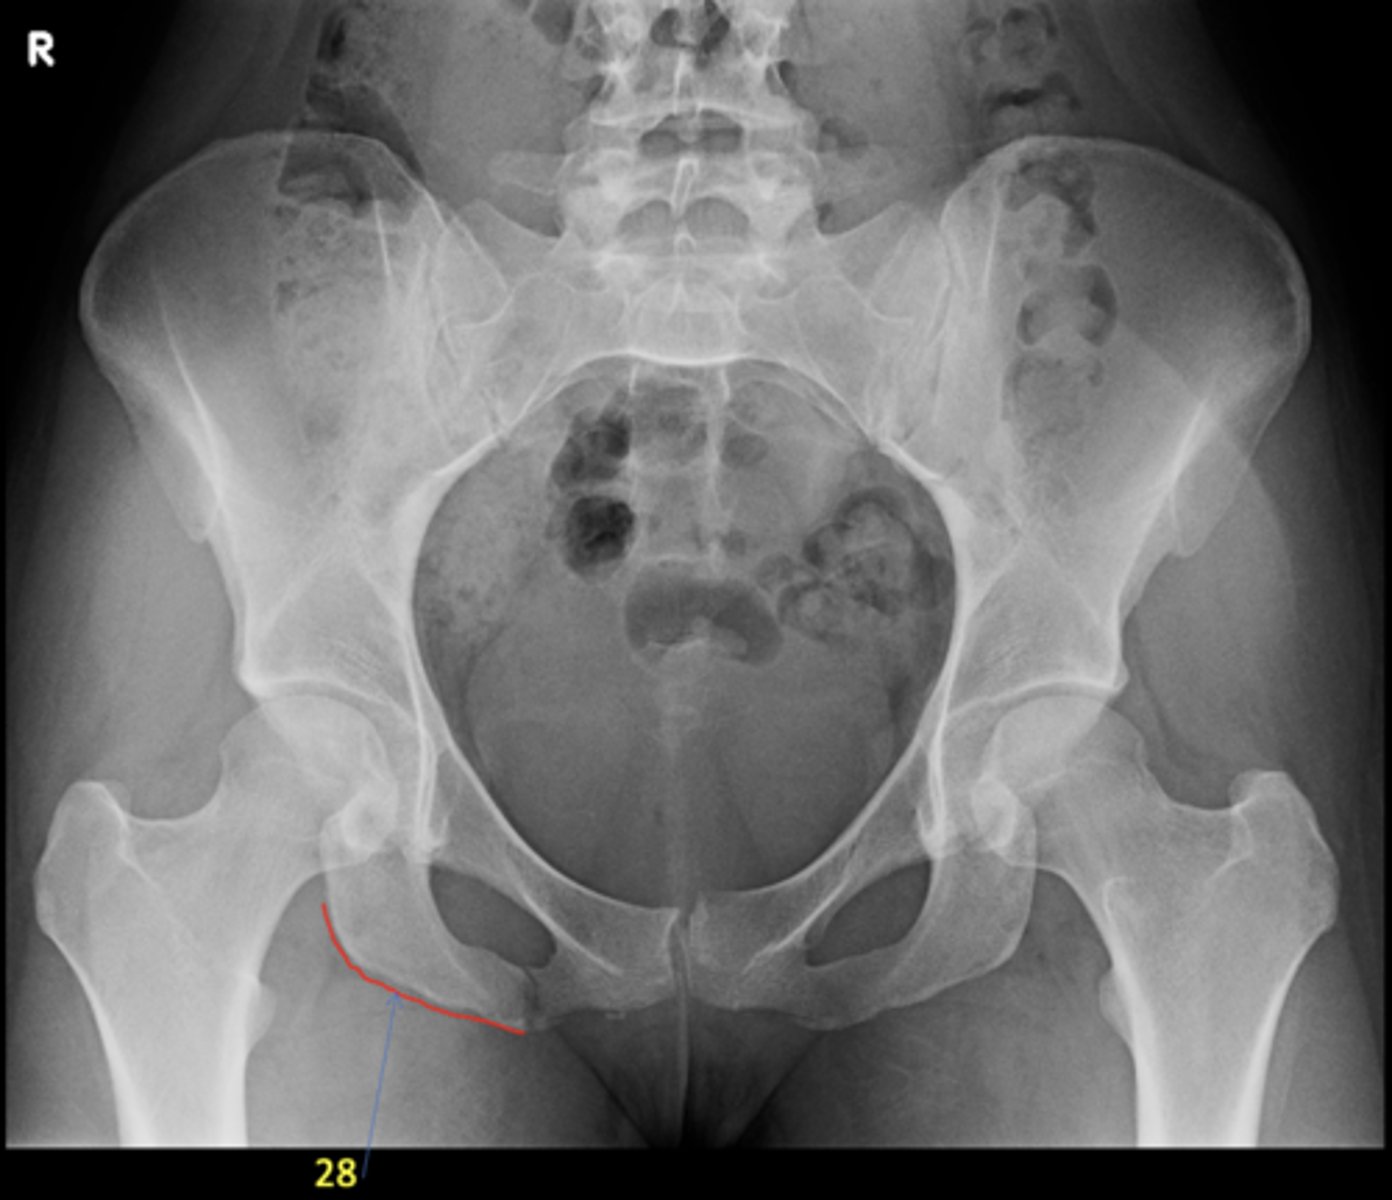

1

AP pelvis

View?

<p>View?</p>

24

25

New cards

Right ischial tuberosity

ID 28

<p>ID 28</p>